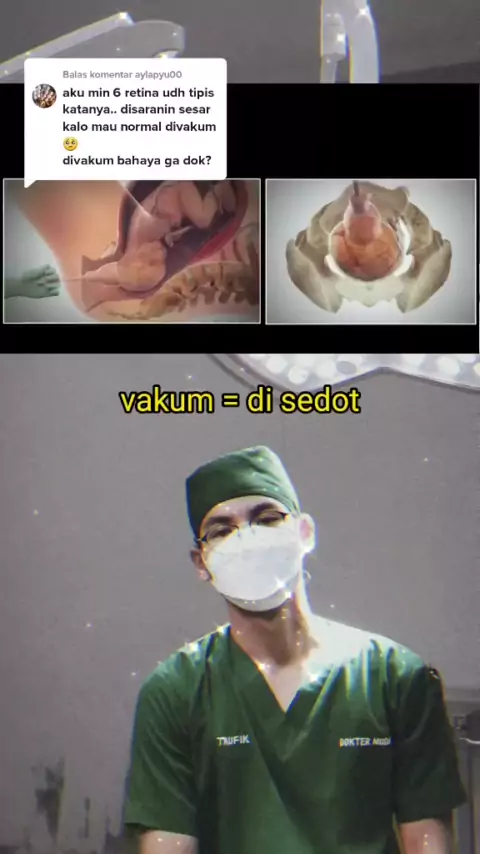

Balas @aylapyu00 Loh kok istri saya di sedot? "respon suami kalau liat istrinya melahirkan"